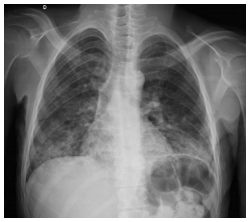

Paciente de 30 anos, com paralisia cerebral, trazido para a emergência com

dificuldade respiratória, náuseas, vômitos e desconforto abdominal. História de constipação crônica.

Sem febre e hemograma sem leucocitose, nem desvio. Com base no Rx de tórax abaixo, qual a maior

probabilidade diagnóstica?